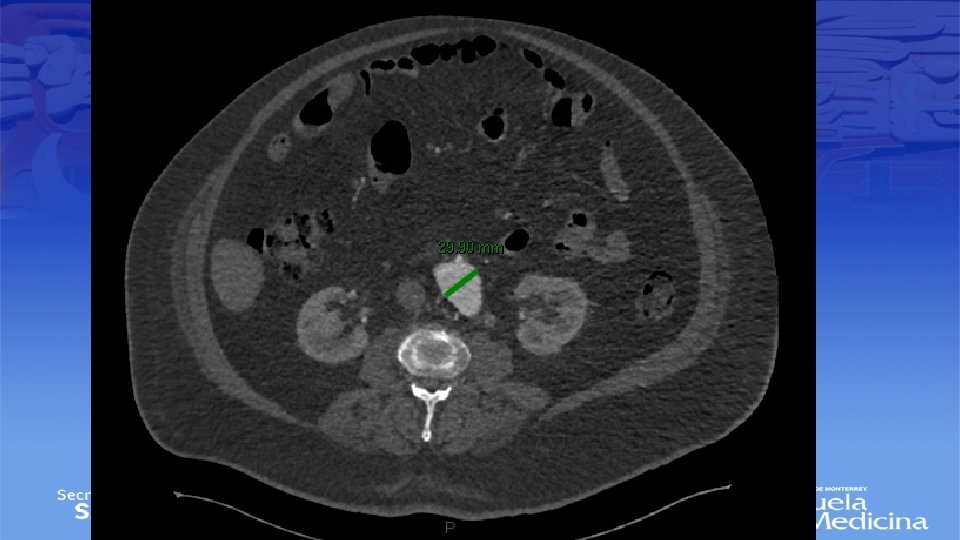

Angiotac

Impresión Diagnóstica • IDX: Aneurisma Poplíteo bilateral

Tamizaje • Aneurisma poplíteo único tiene un riesgo de presentar aneurisma abdominal en 40% de los casos • Aneurisma Bilateral hasta en un 70% de los casos • Guías Clínicas – Masculinos con tabaquismo + en edades de 65 -75 años – Femeninas con antecedentes familiares de aneurismas

Diagnostico • Ultrasonido Doppler, Angiotac, angioresonancia • Arteriografía es mas apropiada para sintomatología aguda